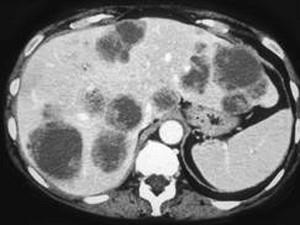

问题 男,54岁,患者一年前行结肠癌手术,癌胚抗原增高,影像检查如图,最可能的诊断是 ( )

选项 A、多发性肝囊肿 B、肝淋巴瘤 C、结肠癌肝转移 D、多发性肝脓肿 E、多发结节性肝癌

答案 C